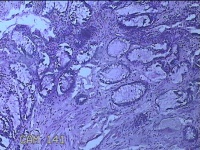

肛门肿物

性别

男

年龄

40岁

临床诊断

混合痔

一般病史

反复肛门肿物突出15年。

标本名称

大体所见

灰白暗红色肿物0.7x0.5x0.2cm一个,表面糜烂。

脱水、透明,浸蜡、脱蜡效果不佳,制片质量差。